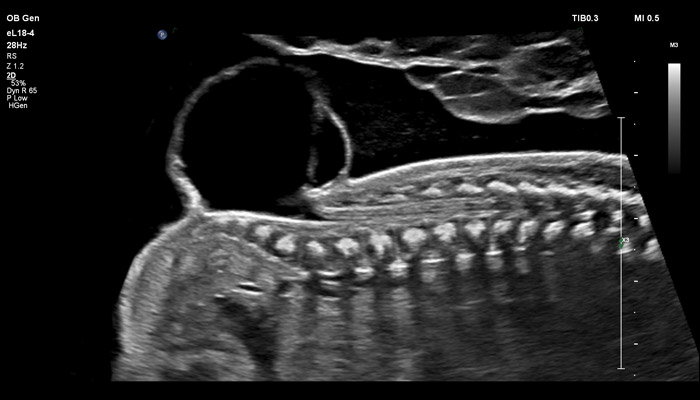

Начало новой жизни - это всегда особое время! Ультразвуковые решения Philips в области акушерства разработаны для того, чтобы позволить врачам сосредоточиться на здоровье каждой будущей мамы. Разработанные для обеспечения клиницистов дополнительной информацией ультразвуковые решения Philips позволяют получать не только детальную визуализацию анатомии плода уже в первом триместре, но и помогают оптимизировать рабочий процесс врача. Применение eL18-4 в I триместре беременности Сегодня ультразвуковая диагностика используется для выявления генетических аномалий, внутриутробных пороков, оценки жизнеспособности плода и определения срока беременности, как наиболее эффективный метод. Ультразвуковое исследование плода в первом триместре (до 13 недель 6 дней беременности включительно) является наиболее точным методом. В течение многих десятилетий трансвагинальный метод ультразвукового исследования был «золотым стандартом» диагностики в акушерстве. Сегодня линейный матричный датчик может стать альтернативой общепринятому трансвагинальному методу оценки состояния плода и репродуктивных органов женщины. Детальная анатомия плода и ранняя диагностика пороков в I триместре Ультразвуковое исследование является основным методом визуализации для оценки врожденных аномалий плода. Линейный матричный датчик eL18-4 позволяет получить детальную информацию об анатомии плода и выявить пороки на ранней стадии развития. Сверхширокополосная PureWave матрица датчика генерирует частоты в диапазоне 2-22 МГц, что формирует одинаково высокоинформативные, четкие изображения по всей глубине сканирования до 14 см.

До введения высокочастотных линейных датчиков точная ультразвуковая диагностика мочевой системы плода была доступна в основном после 16-17 недель беременности. Новая технология еL18-4 позволяет проводить раннюю морфологическую оценку плода уже в первом триместре. Клинический случай с применением eL18-4 демонстрирует, что кортико-медуллярная дифференцировка почек плода возможна на 14 неделе беременности”.

Использование линейного матричного датчика eL18-4 при осмотре беременных в I триместре, особенно на ранних сроках, позволяет ограничиться трансабдоминальным сканированием вместо трансвагинального и при этом получить максимально полную диагностическую информацию. Отсутствие полостного исследования чрезвычайно важно для соблюдения принципа ALARA – использования минимальной необходимой мощности для безопасности пациента. Благодаря применению мультичастотного датчика с диапазоном от 2 до 22 МГц через переднюю брюшную стенку хорошо определяется эмбрион длиной 3 мм, что соответствует шестой неделе беременности. В конце I триместра с eL18-4 достаточно отчётливо визуализируется четырёхкамерный срез сердца, мочевой пузырь и сосуды пуповины, которые, как правило, определяются только при трансвагинальном сканировании.

Во II триместре беременности высокая разрешающая способность eL18-4 позволяет детально изучить структуру органов и тканей и увидеть многие нюансы, которые при работе другими датчиками не обнаруживались или становились очевидны в более поздние сроки. Например, у 19-недельного плода визуализируется перегородка носа, мышцы языка, диафрагма между грудной и брюшной полостью, на 20-й неделе чётко определяются оболочки спинного мозга и уретра, а на 24-й – хорошо дифференцируются корень лёгкого, борозды и извилины мозжечка и многие другие структуры.